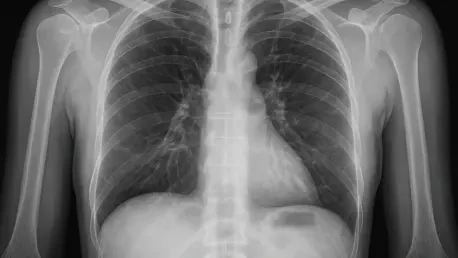

Conventional diagnostic approaches to chest imaging, while precise in minimizing false positives, suffer from a critical flaw: their low sensitivity in detecting radiolucent objects. Radiologists, relying on standard CT scans, achieve a detection rate of only 36% in confirmed cases of foreign body aspiration, a statistic that reveals the profound challenge of identifying anomalies that do not contrast sharply with surrounding tissues. This gap often means that patients endure prolonged uncertainty, with symptoms misattributed to other conditions until more invasive tests are conducted. The stakes are high, as delayed diagnosis can escalate minor issues into emergencies requiring urgent intervention. The inherent limitations of human visual analysis in such nuanced scenarios highlight why traditional methods, despite their strengths in other areas, are insufficient for this specific medical hurdle, pushing the field toward innovative alternatives.

In a remarkable stride forward, an AI-powered diagnostic tool developed by researchers has demonstrated an extraordinary ability to detect radiolucent foreign bodies in chest CT scans, achieving a sensitivity rate of 71% compared to a mere 36% for experienced radiologists. This significant disparity underscores the technology’s potential to transform how hidden threats are identified in clinical settings. Evaluated against a set of 70 scans, including confirmed cases validated through bronchoscopy, the AI not only excelled in spotting elusive objects but also maintained a balanced diagnostic performance with a precision of 77% and an F1 score of 74%, far outpacing human scores. This capability to flag potential issues with greater accuracy offers a lifeline in situations where time is critical, reducing the likelihood of missed diagnoses. The implications of such performance are profound, signaling a shift toward more reliable detection methods in respiratory care.

Equally striking is the AI’s capacity to handle the subtleties of chest imaging that often confound human observers, providing a level of consistency that is difficult to achieve manually. By focusing on minute textural and morphological differences, the system identifies anomalies that blend into the complex anatomy of the airways, a task that challenges even the most trained professionals. This superior detection rate does not just represent a numerical advantage but translates into real-world benefits, such as earlier interventions that can prevent complications like airway blockages or chronic infections. While the tool does produce some false positives, its overall balance ensures that clinicians are not inundated with unnecessary alerts, maintaining a practical approach to diagnostics. This advancement stands as a testament to how technology can address longstanding gaps in medical imaging, offering a new benchmark for accuracy in identifying life-threatening conditions.